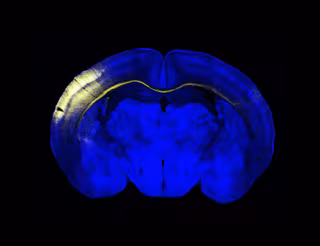

Archivo - Sección horizontal del cerebro del ratón. Un grupo de neuronas de la corteza iluminadas en amarillo extienden sus axones a través del cuerpo calloso para conectar con el hemisferio contralateral.

Archivo - Sección horizontal del cerebro del ratón. Un grupo de neuronas de la corteza iluminadas en amarillo extienden sus axones a través del cuerpo calloso para conectar con el hemisferio contralateral. - CNB/ CSIC - Archivo

Hasta el momento, se había observado la presencia de esos axones, pero ahora los investigadores han demostrado en ratones las propiedades funcionales de esos axones que cruzan y hacen sinapsis con el otro hemisferio. Estos conectan especialmente información táctil de las partes de la línea media y generan una representación o activación idéntica de la información en ambos lados, permitiendo procesar la información sensorial de manera continua.

En este trabajo, cuyo primer autor es Roberto Montanari, han conseguido describir de forma precisa el circuito completo que comunica ambos hemisferios cerebrales: la información percibida ante un estímulo sensorial viaja a través del cuerpo calloso y es procesada específicamente en una región muy concreta de la corteza somatosensorial primaria, en el ratón los barriles de la fila A (RowA).